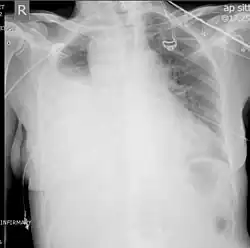

A chest X-ray is the most common technique used to diagnosis a hemothorax.[23] X-rays should ideally be taken in an upright position (an erect chest X-ray), but may be performed with the person lying on their back (supine) if an erect chest X-ray is not feasible. On an erect chest X-ray, a hemothorax is suggested by blunting of the costophrenic angle or partial or complete opacification of the affected half of the thorax. On a supine film the blood tends to layer in the pleural space, but can be appreciated as a haziness of one half of the thorax relative to the other.[5] A small hemothorax may be missed on a chest X-ray as several hundred milliliters of blood can be hidden by the diaphragm and abdominal viscera on an erect film. Supine X-rays are even less sensitive and as much as one liter of blood can be missed on a supine film.[24]

Ultrasonography may be used to detect hemothorax and other pleural effusions. This technique is of particular use in the critical care and trauma settings as it provides rapid, reliable results at the bedside.[23] Ultrasound is more sensitive than chest x-ray in detecting hemothorax.[25] Ultrasound can cause issues in people who are morbidly obese or have subcutaneous emphysema. When CT is unavailable in the current setting or the person cannot be moved to the scan, ultrasound is used.[3]

Computed tomography (CT or CAT) scans may be useful for diagnosing retained hemothorax as this form of imaging can detect much smaller amounts of fluid than a plain chest X-ray. However, CT is less used as a primary means of diagnosis within the trauma setting, as these scans require a critically ill person to be transported to a scanner, are slower, and require the subject to remain supine.[23][26]